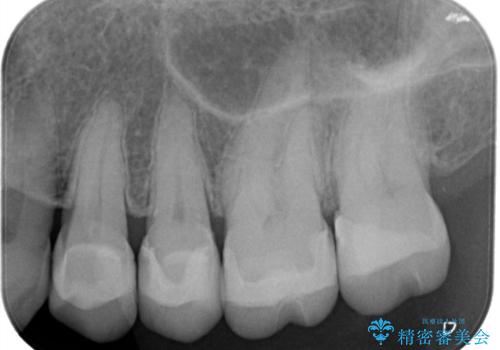

- 昔入れた銀歯のやりかえを主訴に来院されました。

セラミックインレーにて修復を行いました。

歯の強度を高めるためセラミッククラウンの提案もさせていただきましたが、患者様の希望でセラミックインレーにて修復を行なっております。